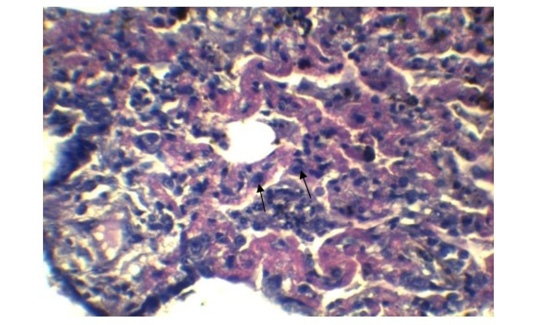

Expanded alveolar wall due to prominent type-II pneumocytes. (H&E x 40).